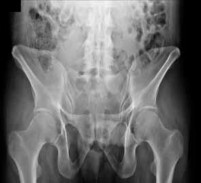

Figure 7Figure 7 is the pelvic radiograph of a 33-year-old man involved in a high-speed automobile crash. Examination reveals a blood pressure of 90/50 mm Hg and a pulse rate of 120/min. Radiographs of the chest and lateral cervical spine are normal. A CT scan of the abdomen does not reveal any intraabdominal bleeding. What is the most appropriate management for the pelvic fracture?